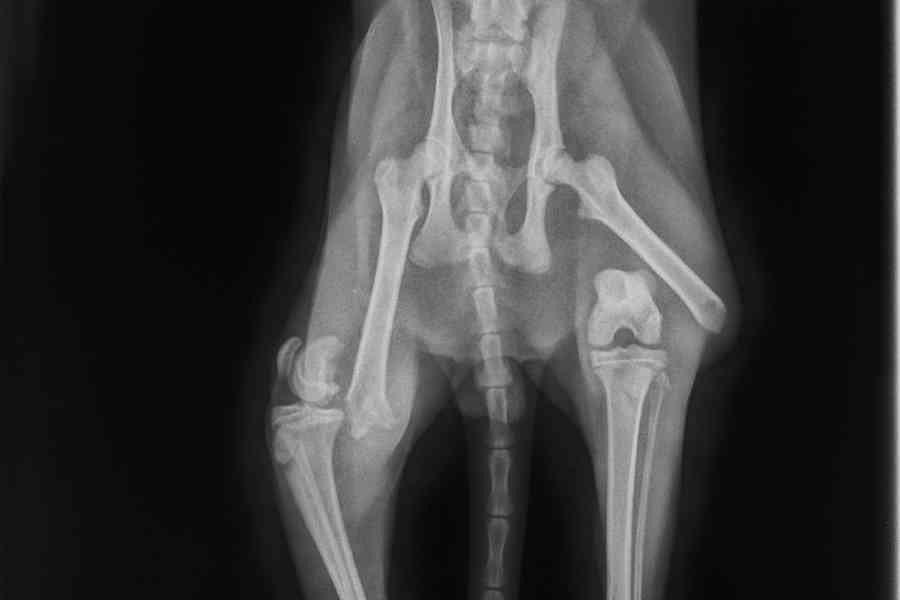

Die Diagnose traf uns mit voller Wucht: Beide Oberschenkel sind gebrochen.

Für Tiger bedeutete das eine sofortige Einweisung in die Klinik. Eine aufwendige Operation bei einem erfahrenen Chirurgenteam war seine einzige Chance seine Beine zu behalten und jemals wieder schmerzfrei laufen, springen und spielen zu können.